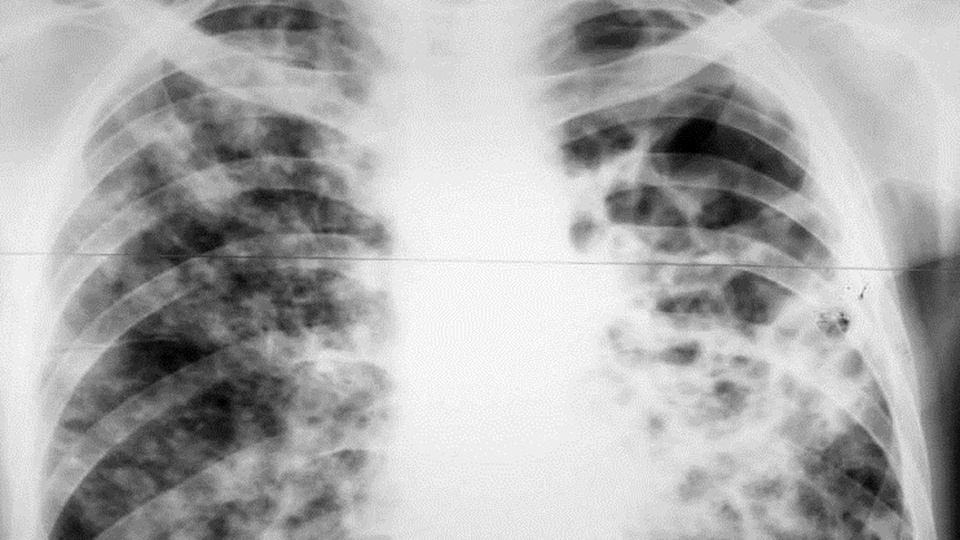

Пациентка с открытой формой туберкулеза находилась на лечении в профильном диспансере, но не долечилась и самовольно покинула больницу. Так как женщина ведет асоциальный образ жизни и игнорирует указания врачей, решение о принудительной госпитализации вынесли в судебном порядке.